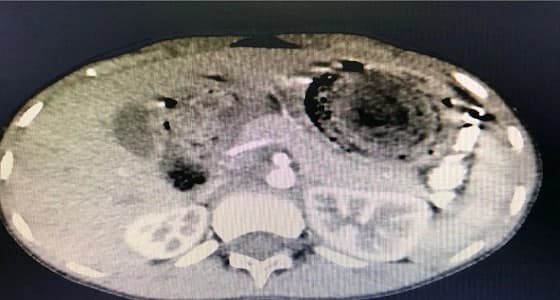

أجري فريق طبي بمستشفى الولادة والاطفال بمدينة بريدة، جراحة بالمنظار لأول مرة بالقصيم، لاستئصال كتلة محسوسة ببطن طفل، بعد استخدام المنظار لأول مرة بالقصيم في مثل هذه الحالات، وكللت العملية بالنجاح واستقرار وضع المريض الصحي. وقال حمد الشمري مدير المستشفى الصيدلي، إن الطفل الذي يبلغ من العمر 9 سنوات كان قد راجع المستشفى، ويعاني منكتلة محسوسة في البطن وبإجراء الفحوصات اللازمة من اشعة فوق صوتية و اشعة طبقية اظهرت وجود كتلة كبيرة تملأ المعدة من الشعر والخيوط واجسام بلاستيكية، مشيرا إلى أنه تم اجراء تنظير للبطن من قبل طاقم جراحي برئاسة الدكتور شان بوك ومساعده الدكتور هشام سيد وتم استئصال الكتلة.